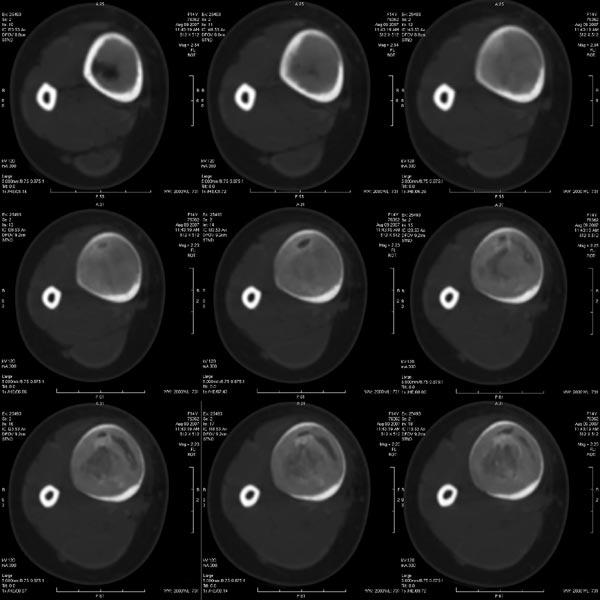

女性,14岁。自觉右胫骨下段前缘隆起。x线示:右胫骨干骨膨隆,骨皮质压迫性变薄。

胫骨中段皮质内环绕并突入髓腔膨胀性生长的软组织密度病灶,内缘粗糙,外缘光滑无中断,病灶内可见小点状钙化.未见骨膜反应及瘤骨;软组织显示如常,未见肿块及异常密度.

考虑:胫骨中段良性肿瘤或肿瘤样病变,骨纤可能大.

右胫骨中段囊性、膨胀性改变,病变呈中心性,沿骨的纵轴生长,病变区骨皮质明显变薄,骨包壳完整,无中断,病变边缘无明显硬化,未见明显骨膜反应,周围软组织无肿胀。首先肯定的是骨良性病变(良性骨肿瘤或肿瘤样病变。有以下几种可能:

1 骨囊肿:发生于骨干的囊肿,可沿髓腔的长轴发展,在髓腔形成长囊状骨折破坏区,但骨囊肿病变周围一般都有明显边缘硬化,易发生病理性骨折,这点不支持。

2 动脉瘤样骨囊肿:好发于长骨干骺端,多偏心生长于骨干的一侧,易多囊、分隔、有嵴(皂泡样),中心型可沿纵轴生长,呈溶骨性囊样,但囊内也多含粗或细的骨小梁,边缘也有硬化环包绕。也不太支持。

5 骨纤维异常增殖症:可有囊状膨胀性、磨玻璃样、丝瓜瓤样及虫蚀状多种表现,囊状膨胀性可有类似改变,但范围一般较广,也常绕硬化环。

总之,我感觉骨肿瘤及肿瘤样变鉴别诊断很困难,有时病变表现不典型时影像很难确诊,此病例我的诊断是:骨巨细胞瘤>骨血管瘤>骨纤。